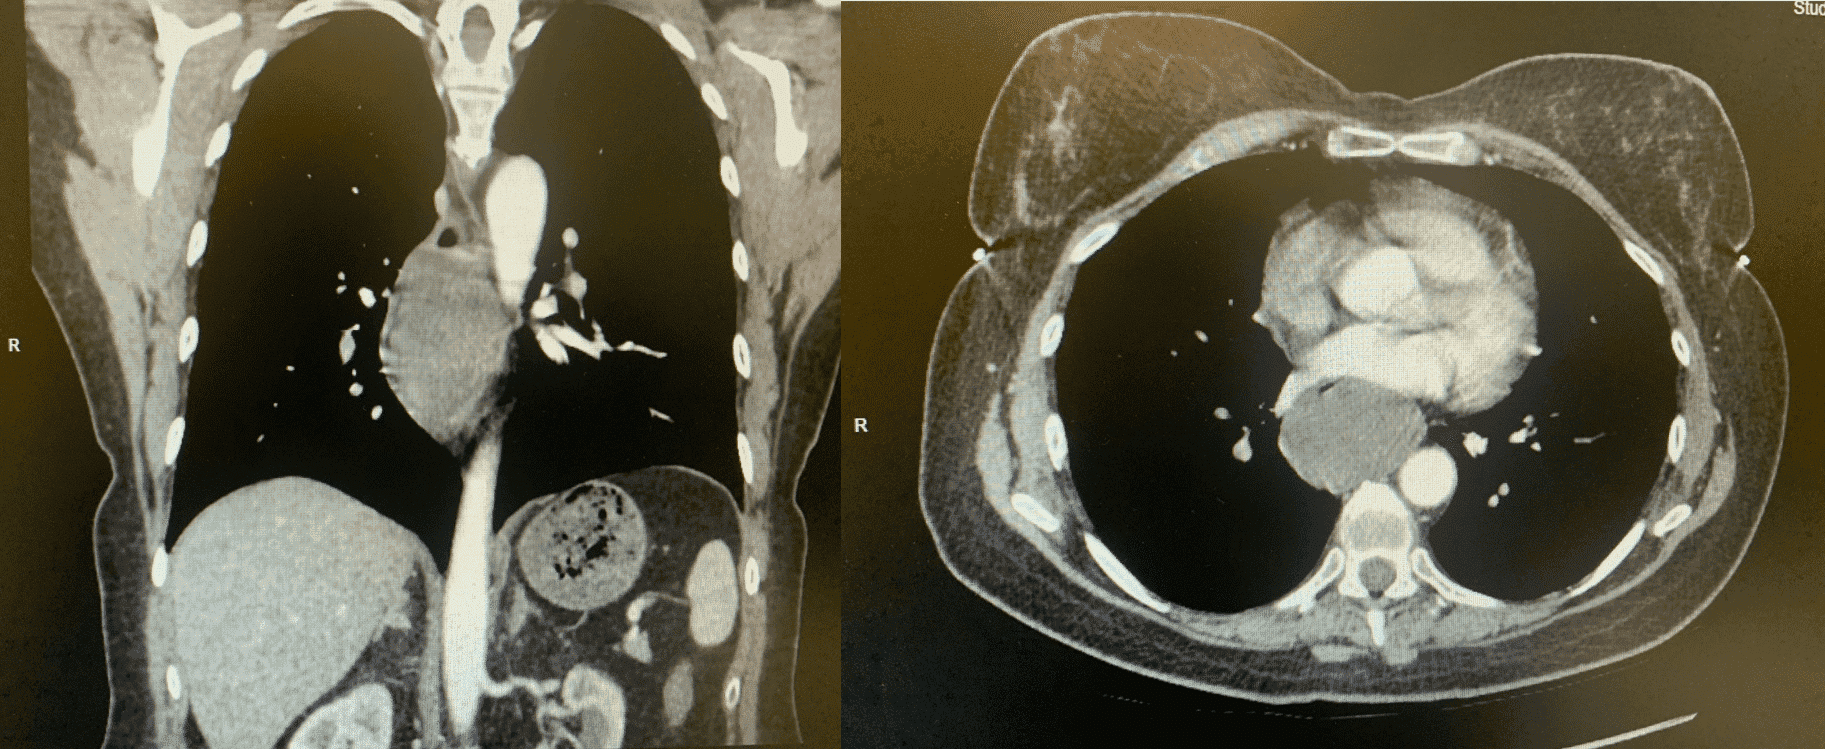

КТ з внутрішньовенним контрастуванням корисна для подальшого диференціювання утворення з іншими прилеглими структурами середостіння, а також визначення ступеня ураження довжини стравоходу. На КТ пухлина часто описується як округле, ексцентричне, рівномірно щільне, іноді долькове, гладке утворення навколо стінки стравоходу (зобр. 3).[3,7]

КТ-візуалізація може бути корисною для визначення проведення подальших діагностичних або хірургічних методів, якщо це показано.

Зображення 3. КТ з внутрішньовенним контрастуванням показує циркулярне, ексцентричне, рівномірно щільне, іноді долькове, гладке утворення навколо стінки стравоходу.